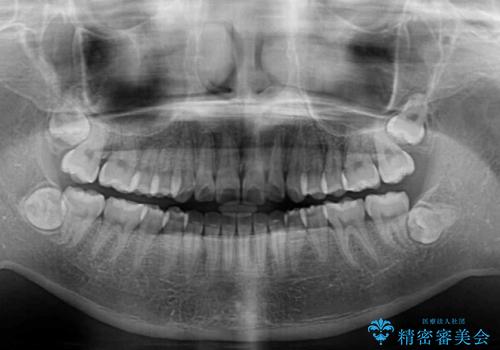

- 前歯の叢生を気にして来院された患者様です。

奥歯の咬み合わせを見ると、上顎が下顎に対して相対的に前方にあり、上下の前歯が接触していない状態でした。

咬み合わせを改善するためには、上顎臼歯を後方に移動させた咬み合わせにする必要があります。

インビザライン単体で改善することも可能ですが、咬合力が強く、単位で達成する可能性が低いと考えられたため、カリエール・ディスタライザーという補助装置を併用して、より確実性を上げることとしました。

奥歯の咬み合わせを改善しながら、並行してインビザラインで歯列を整えることとしました。

カリエールディスタライザーを併用したことで、確実かつ短期間で治療を終えることができました。